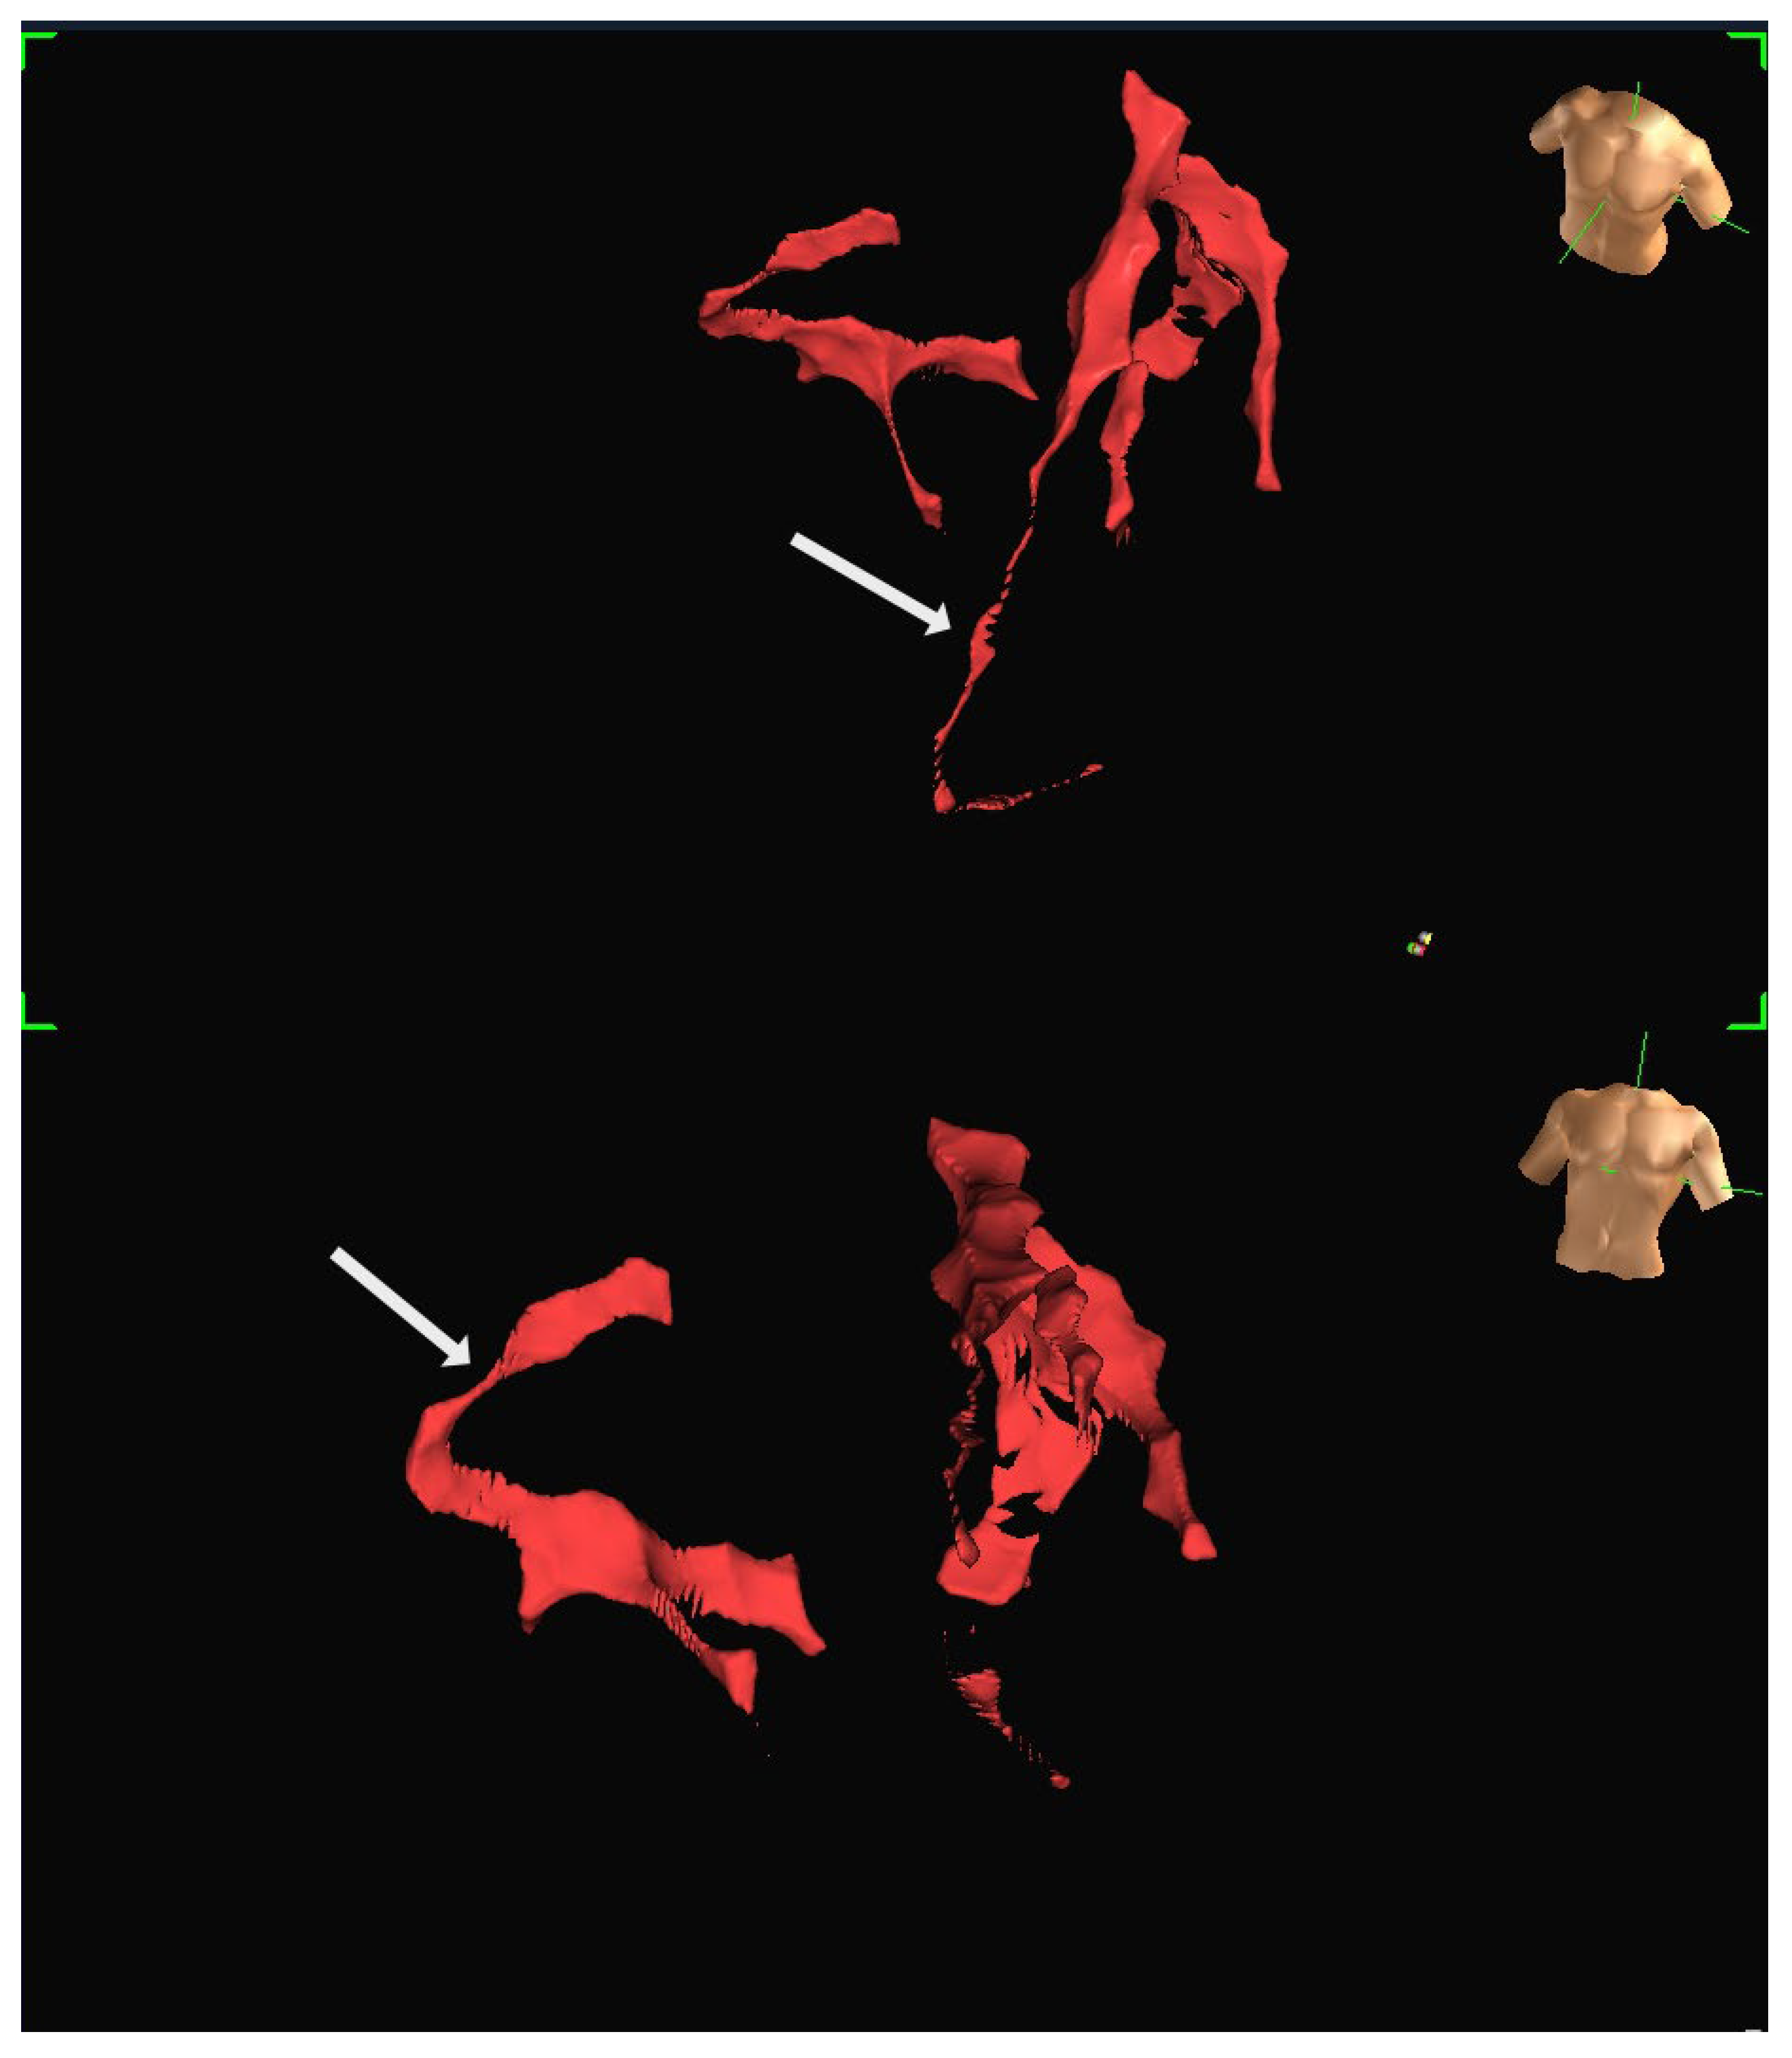

To address these challenges, adjunctive imaging modalities have been adapted to enable ultra-low contrast PCI. Intravascular ultrasound (IVUS) provides detailed cross-sectional images without reliance on contrast media (Figure 1) and is recommended in complex interventions [5,6]. OCT provides high-resolution plaque characterisation and stent assessment (Figure 2), but requires flushing, typically with contrast media; however, substitutes such as low-molecular-weight dextran and heparinised saline have shown promise as alternatives [51,52,53,54]. DCR software overlays a live coronary roadmap onto the fluoroscopic image, enabling navigation of coronary tools and stent delivery without repeated contrast injections (Figure 3) [7,55]. While these modalities provide valuable anatomical information, they remain dependent on fluoroscopic platforms and do not eliminate contrast use entirely, highlighting the potential role for complementary navigation technologies such as EAMS.

Figure 2. OCT of the left anterior descending (LAD) artery. Red arrow indicates the referenced OCT segment correlating with the angiogram. OCT reveals severe proximal LAD stenosis not readily apparent on angiography.